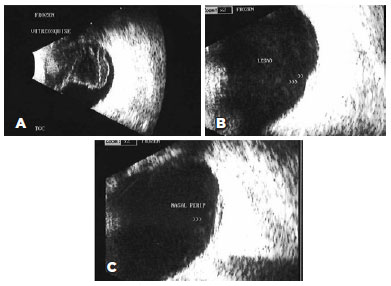

The ultrasonographic characteristics observed in our patients are presented in table 1. Vitritis (Figure 1B), which appeared as a punctate vitreous echo on ultrasonography, was detected in all 47 eyes (100%) and was either diffuse (40 eyes, 85.1%) or localized (7 eyes, 14.9%). PVD (Figure 1C) was identified in 36 eyes (76.6%) and was either partial (12 eyes, 25.5%) or total (23 eyes, 48.9%). No sign of PVD was noted in 11 eyes (23.4%). Of the 36 eyes with PVD, 35 (97.2%) exhibited hyaloid thickening, and 4 (11.1%) exhibited adherence to the exudative lesion (Figure 1D). Vitreoschisis (Figure 2A) and chorioretinal thickening (Figure 2B) were each identified in 12 eyes (25.5%), while perilesional non-rhegmatogenous retinal detachment (Figure 2C) was observed in 5 eyes (10.6%). A comparison of information from the questionnaire with the ultrasonography findings revealed that the latter could accurately demonstrate the location of the exudative focus in 12 eyes (25.5%).

13-fig02.jpg)

Posterior vitreoschisis is defined as delamination in 2 or more leaflets of the posterior vitreous cortex, the outermost of which is the true posterior hyaloid membrane. This phenomenon is very frequently observed in eyes affected by retinal vascular diseases and vitreous hemorrhage (including proliferative diabetic retinopathy). However, this condition has only recently been described in uveitis(22). In our series, we observed posterior vitreoschisis in 12 eyes (25.5%).

During the acute phase of toxoplasmosis, B-mode ultrasonography can observe small increases in retinochoroidal thickness that correspond to the sites of exudative lesions and perilesional edema. In our study, we observed an increase in retinochoroidal thickening in 12 patients (25.5%), 5 (10.6%) of whom had perilesional retinal detachment. Consistent with our finding, Hercos et al.(23) reported focal retinochoroidal thickening in 28.6% of patients. The use of a proper ocular ultrasonography technique can improve the clinical understanding of the relationship between the posterior vitreous cortex and retina. However, OCT remains appropriate for detailed fine morphological studies. In cases involving opaque media or another contraindication for OCT, the addition of ultrasonography not only enables a valid evaluation but also provides useful information related to the vitreomacular interface(24).

Posterior uveitis secondary to toxoplasmosis may induce thickening of the hyaloid membrane, enhanced adhesions in the exudative foci, and changes in the vitreous that promote contraction against the retinal direction, along with an initially partial detachment of the vitreous that later progresses to total detachment. Our series of cases included 12 eyes in which ultrasonography revealed chorioretinal thickening; of these, 6 had no PVD and 3 had partial PVD (adherence to the exudative lesion in 1 of 3). Therefore, 7 eyes (58.3%) with thickening exhibited some degree of vitreoretinal adhesion to the active chorioretinal focus.